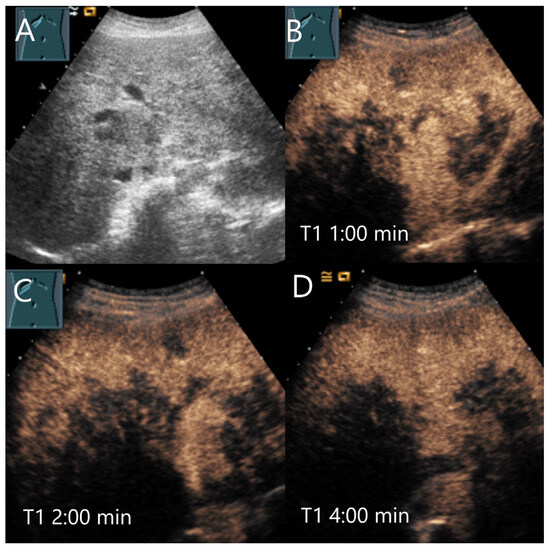

Figure 3.

Cavernous hemangioma. Female patient. Incidental finding of a 40 × 32 mm heterogeneous hypoechoic FLL (A). The CEUS shows arterial marginal hyperenhancement after 14 s (B) and homogeneous AP hyperenhancement after 1:00 min (C). Decreasing heterogeneous hyperenhancement after 2:16 min (D) and 3:07 min (E). After 4:30 min (F), there is a clear hypoenhancement. Clinical ultrasound revealed the diagnosis of a hemangioma. Histologically, a cavernous hemangioma was confirmed.